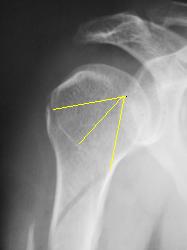

А что по "поводу головки" плечевой кости в "районе большого бугорка".

ИзображениеИзображение

Думаю, что это начало спирали.

А еще это похоже на перелом по типу Хилл-Сакса большого бугорка.

Мне видится, что перелом идет так

Мне кажется, что импрессионного перелома бугорка (повреждение Хилл-Сакса) здесь нет. При данном повреждении импрессия более выражена. Типичный перелом Хилл-Сакса выглядит примерно так.

Хотя, конечно, аксиальная проекция всё бы расставила по своим местам. На мой взгляд, второго перелома в области бугорка здесь нет.